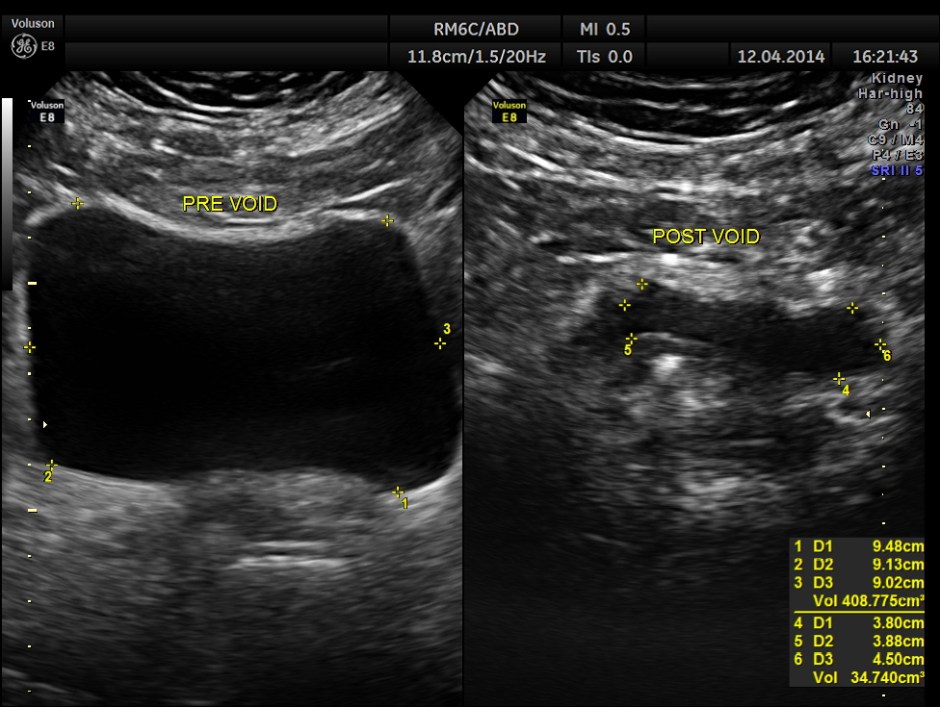

Post void bladder was studied and showed the following .

Lo and behold – a distal right ureteric calculus is clearly seen now .

Usually we pick up all ureteric calculi and distal ureteric pathologies with a full bladder . Usually distal ureteric calculus will cause some amount of obstructive features in the ureter and the kidney . That was also absent in this patient .

But occasionally like this patient , the distal ureters can be compressed with a full bladder and such findings could be missed unless we do a post void study, especially when they have a LUTS symptoms . In this patient the bladder wall also showed mild thickening.